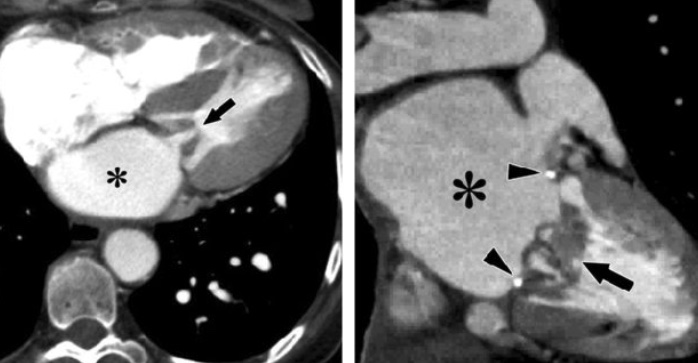

Insuffisance Tricuspide

- Sur insuffisance cardique ou HTP avec dilatation des cavités droites

- Dilatation de l’OD

- Dilatation du VD

- Reflux dans les Veines Hépatiques, dilatation de l’IVC